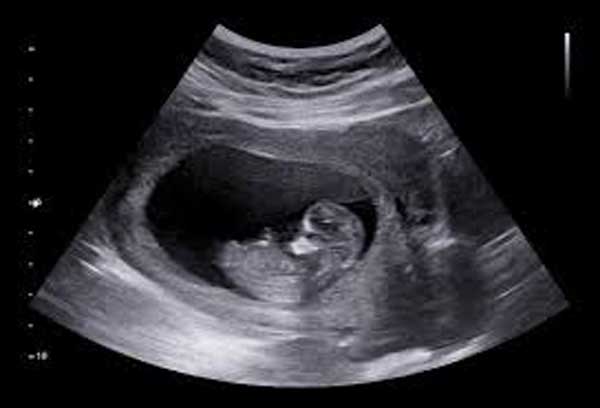

Chiều dài xương cánh tay (Humerus Length – HL) là chỉ số đo chiều dài của xương cánh tay trên của thai nhi, tính từ vai đến khuỷu tay. Thông số này thường được đo cùng với chiều dài xương đùi trong các lần siêu âm nhằm:

Chiều dài xương cánh tay là chỉ số đo chiều dài của xương cánh tay trên của thai nhi